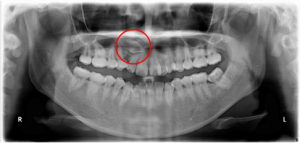

K:はい。埋伏歯とは、歯が歯茎(又は骨)の中に埋まってしまっている状態のことです。皆さんが良くご存知な「親知らず」が最も埋伏歯になりやすい歯になります。

昔に比べてアゴが小さくなってきた現代人は、最後に生えてくる第3大臼歯の生えるスペースが足りなくて、多くの人が大人になって、抜かなくてはならないわけですが、矯正治療が必要になるのは親知らず以外の歯が埋伏してしまうケースですね。

原因は様々ですし、わからないこともあります。たとえば永久歯がまだアゴの中にあるときに、顔や口をぶつけてしまったことによる衝撃が原因だったり、乳歯がむし歯になって早く抜けてしまった結果、隣の歯が動いて本来生える永久歯のスペースがなくなったことが原因になったりします。